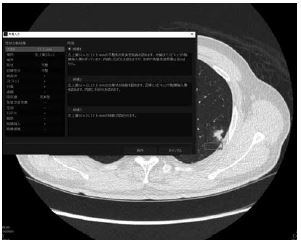

もう一つの機能に肺結節の性状分析がある。肺の場所、性状、サイズなどをまとめて、いくつかの候補で所見にしてくれる優れものである(図4)。この症例では「左肺上葉S1+2に径17.1mm大の不整形の充実性結節を認めます。分葉状でスピキュラや胸膜陥入像を伴っています。内部に石灰化を伴っていますが、空洞や気管支透亮像は含みません。」と表示される。ここまで分析できるなら、この結節の肺癌の可能性を%で出せるようになる未来も近そうだ。